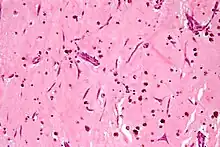

About 20 percent of primary tumors of the heart are malignant in nature.[2] Malignant tumors of the heart include rhabdomyosarcomas, angiosarcomas, myxosarcomas, fibrosarcomas, leiomyosarcomas, reticulum cell sarcomas, desmoplastic small round cell tumor, and liposarcomas. Angiosarcoma is the most common primary cardiac malignancy.[4] It tends to occur in the right atrium and involve the pericardium. Cardiac sarcomas may occur at any age but are more commonly seen in individuals in their 20s to 40s. They occur equally in males and females. Rhabdomyosarcoma is the most common primary cardiac malignancy in children and is more likely than other primary cardiac sarcomas to involve the valves.